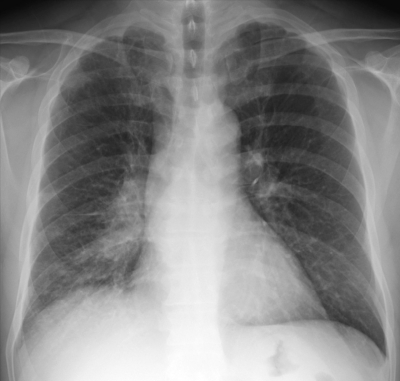

血液所見:赤血球 508 万、Hb 14.8 g/dL、白血球 5,600、血小板 25 万。 血液生化学所見:総ビリルビン 0.6 mg/dL、AST 10 U/L、ALT 21 U/L、LD 425 U/L(基準 176〜353)、尿素窒素 14 mg/dL、クレアチニン 1.2 mg/dL、CEA 2.9 ng/mL(基準 5.0 以下)、SCC 1.2 ng/mL(基準 1.5 以下)、ProGRP 350 pg/mL(基準 81 以下)。CRP 0.3 mg/dL。胸部エックス線写真と胸部CTとを示す。気管支鏡下生検で肺癌と診断された。

肺癌の組織型として最も可能性が高いのはどれか。